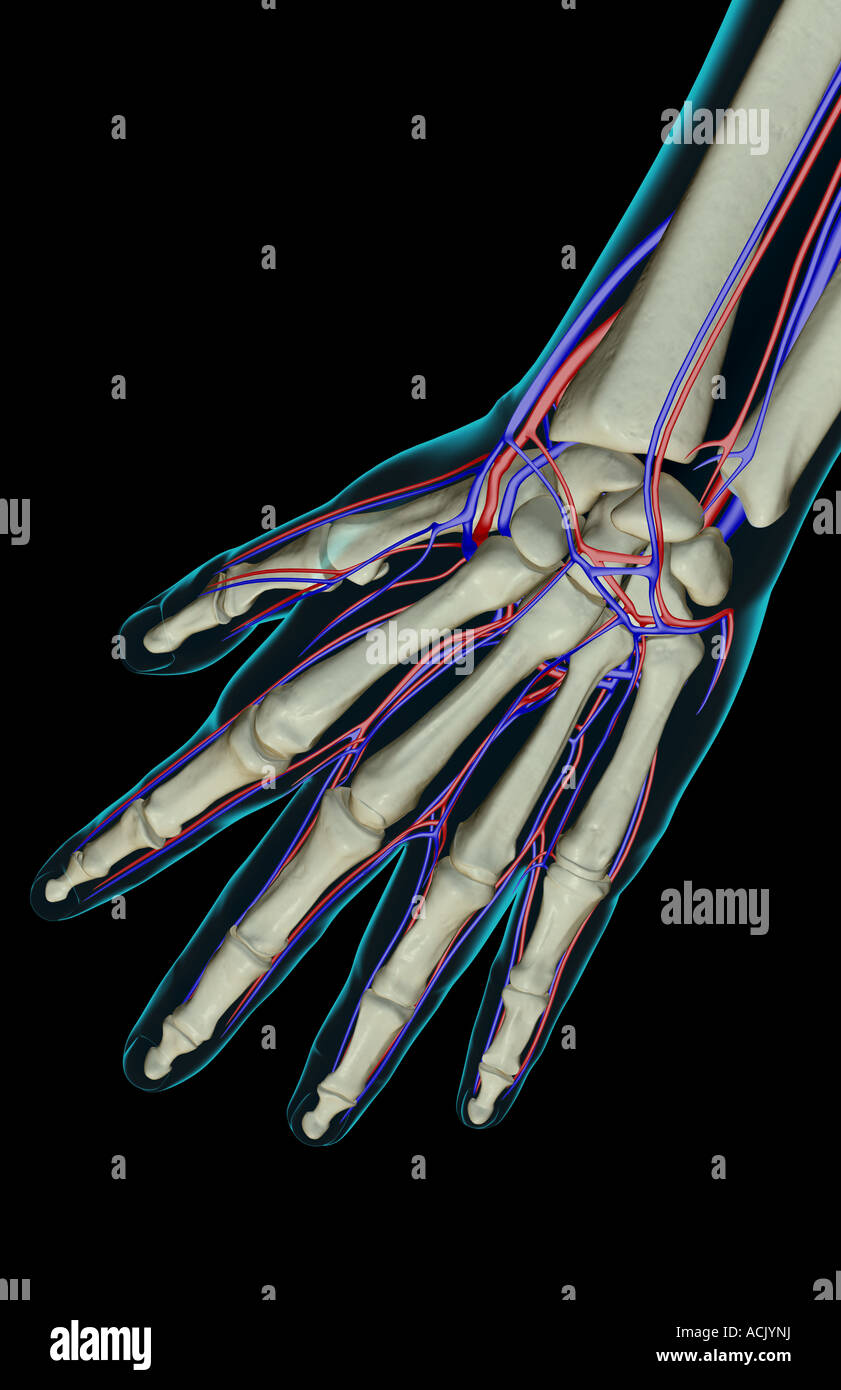

The blood supply of the hand Stock Photohttps://www.alamy.com/image-license-details/?v=1https://www.alamy.com/stock-photo-the-blood-supply-of-the-hand-13174253.html

The blood supply of the hand Stock Photohttps://www.alamy.com/image-license-details/?v=1https://www.alamy.com/stock-photo-the-blood-supply-of-the-hand-13174253.htmlRFACJYNJ–The blood supply of the hand